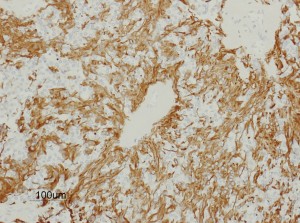

摘出した標本のHE染色です。左側ではperivascular pseudorosette(血管周囲の無核野)がみられ,右側ではependymal tube (ependymal canal) が認められます。

左がGFAP染色、右がMIB-1(Ki-67)染色です。 GFAPは腫瘍血管の周囲の無核野に強陽性です。MIB-1 labelling index が1%以下であり,この上衣腫の増殖能が極めて低いことを示しています。このような高分化型で増殖能の低い上衣腫は脊髄髄内には多いのですが,脳では珍しいものです。ovex中心上衣腫にみられます。